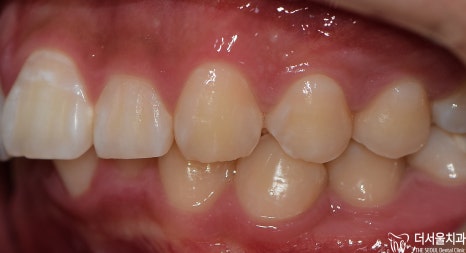

인비절라인 후

구내 사진을 보여드리겠습니다

처음에 보이지 않던

하악 전치부=아래턱 앞니가

이제는 ‘잘’ 보이는 것을 확인해 볼 수 있습니다.

고르지 못했던 치열도

바르게 개선되면서 ‘U’ Shape를 나타냈으며

안쪽 면에 설측 유지 장치를 붙여드리게 되었습니다.